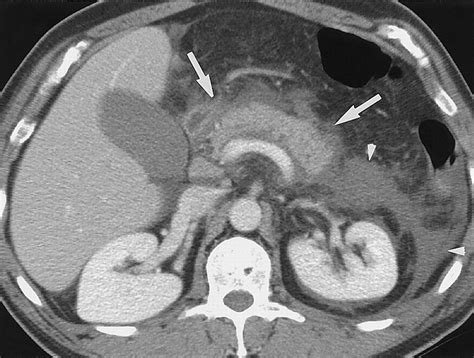

Case Study 2: Pancreatitis

A 45-year-old patient with a history of alcohol abuse presents with severe abdominal pain and vomiting. A CT scan shows peripancreatic fat stranding, pancreatic enlargement, and fluid collections. These findings are indicative of acute pancreatitis, and the patient is managed conservatively with fluid resuscitation and pain management.

Pancreatitis CT Scan